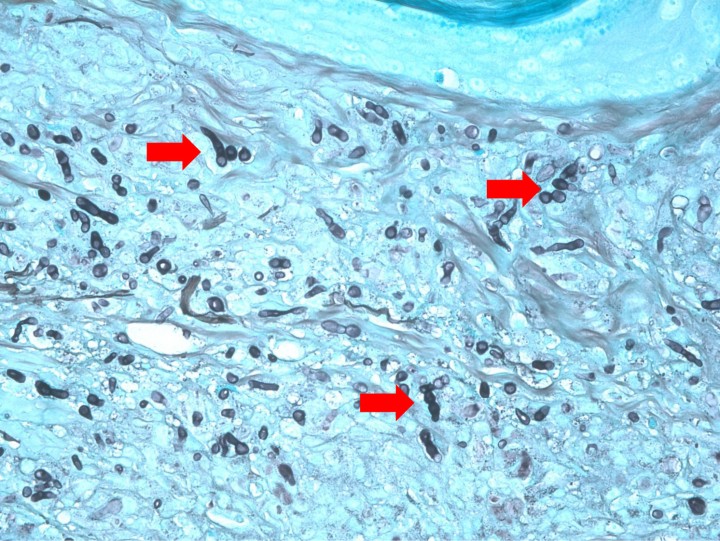

<p>Imagen de la misma preparación de la Figura 6 en la que se aprecian hifas irregulares segmentadas, teñidas con la tinción argéntica de color negro. Grocott x600.</p>

Imagen de la misma preparación de la Figura 6 en la que se aprecian hifas irregulares segmentadas, teñidas con la tinción argéntica de color negro. Grocott x600.

El estudio histológico obtuvo resultados similares en todas las muestras cutáneas. La epidermis mostraba hiperplasia irregular con hiperqueratosis ortoqueratótica y, en la muestra correspondiente a la nariz, se apreciaba una amplia ulceración. La dermis superficial, en especial la zona interfolicular, presentaba un infiltrado inflamatorio denso con predominio de macrófagos, junto con algunos polinucleares neutrófilos y focos linfoplasmocíticos en los que se observaban formaciones esféricas y filamentosas compatibles con formas fúngicas (hifas segmentadas y no pigmentadas). Las tinciones de Grocott y PAS resultaron positivas. El diagnóstico fue de una dermatitis piogranulomatosa de etiología fúngica (feohifomicosis, hialohifomicosis o micosis subcutánea) (Figs. 6-8).